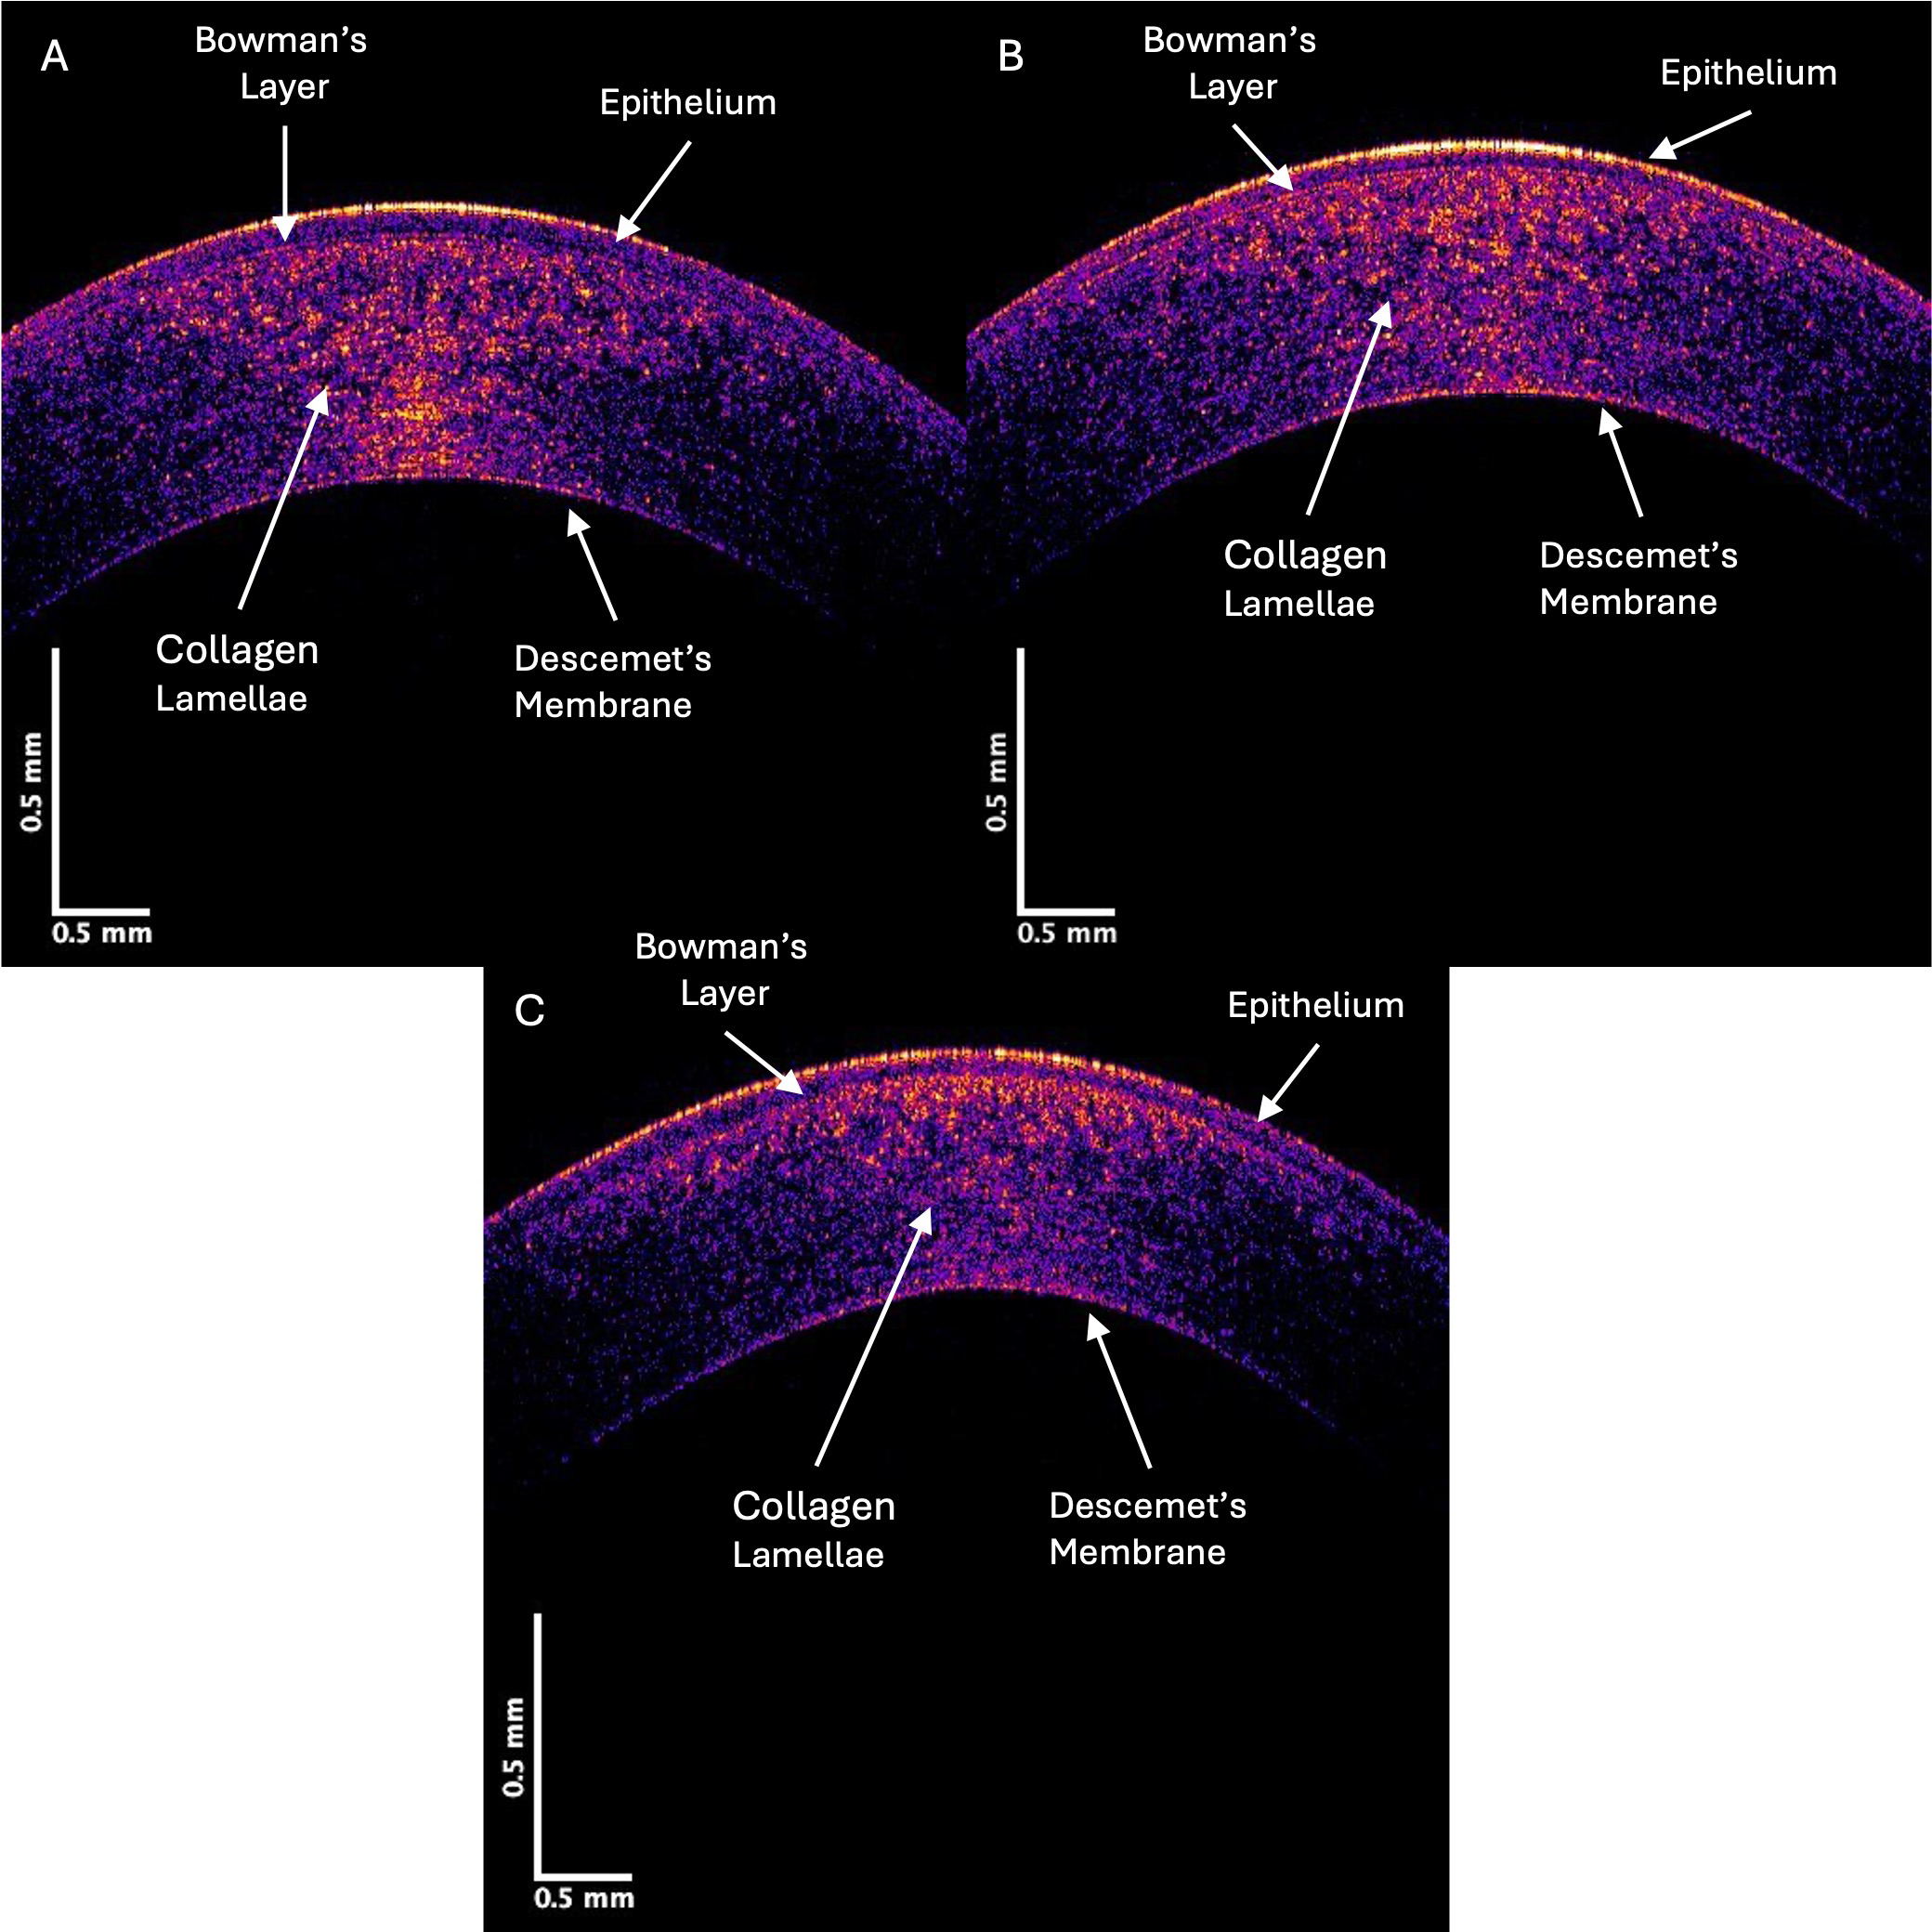

The control and KC cornea images were compared when the grayscale images of the control and KC corneas were separated into individual low (green), medium (blue), and high (red) pixel intensities. Fig. 3 shows the OCT images of the central cornea green channel in typical control (A), Stage II (B), and Stage IV (C) KC corneas. Note the decreased green channel pixel intensity in the posterior central cornea compared to the control and Stages III and IV corneas (Fig. 3).

Fig. 3. Typical green central cornea subchannel images of control (A), Stage II (B), and Stage IV (C) KC corneas. Note the apparent decreased pixel intensity in the posterior region of the corneas in Stages II and IV KC, which suggests a loss of cells (keratocytes) in the posterior cornea.

Pixel intensity versus depth plots for the green channel are shown in Fig. 4. Previous studies on skin demonstrated that the green channel represents the low-intensity cellular contribution to the reflected light [12]. The images in Fig. 4 show that the decreased cellular contribution, presumably of the keratocytes, to the green image decreases in KC.

Fig. 4. The pixel intensity versus depth of the central cornea green channel for control (A), Stage II (B), and Stage IV (C) KC corneas—based on Fig. 3. Note the decreased pixel intensity at depths below 0.1 mm in Stages II and IV in the KC plots suggesting a decrease in the number of keratocytes in posterior corneas. Arrows indicate the points between which the slope was calculated.

The decrease in the initial slope of the pixel intensity versus depth plot for the green channel of Stages I and II KC corneas was statistically greater than that of the control. In contrast, the corneas of Stages III and IV were not statistically different in the data presented in Table 4. These data suggest that the cellular content of the anterior corneas decreases rapidly in the early stages of KC. Table 5 illustrates the pixel intensity of the green channel at a depth of 0.25 mm, which was significantly different for Stage IV but not Stage II at a p-value